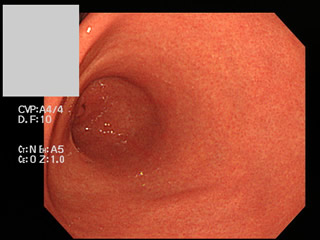

実際の内視鏡の写真を提示します

ピロリ未感染 ピロリ感染(慢性胃炎)

「典型的な所見」なら内視鏡だけで、ピロリの有無を予測できます。

しかし、実際には「どちらとも言えない微妙な場合」も多いです。専門家でも、この写真だけで完全な予測はできません。